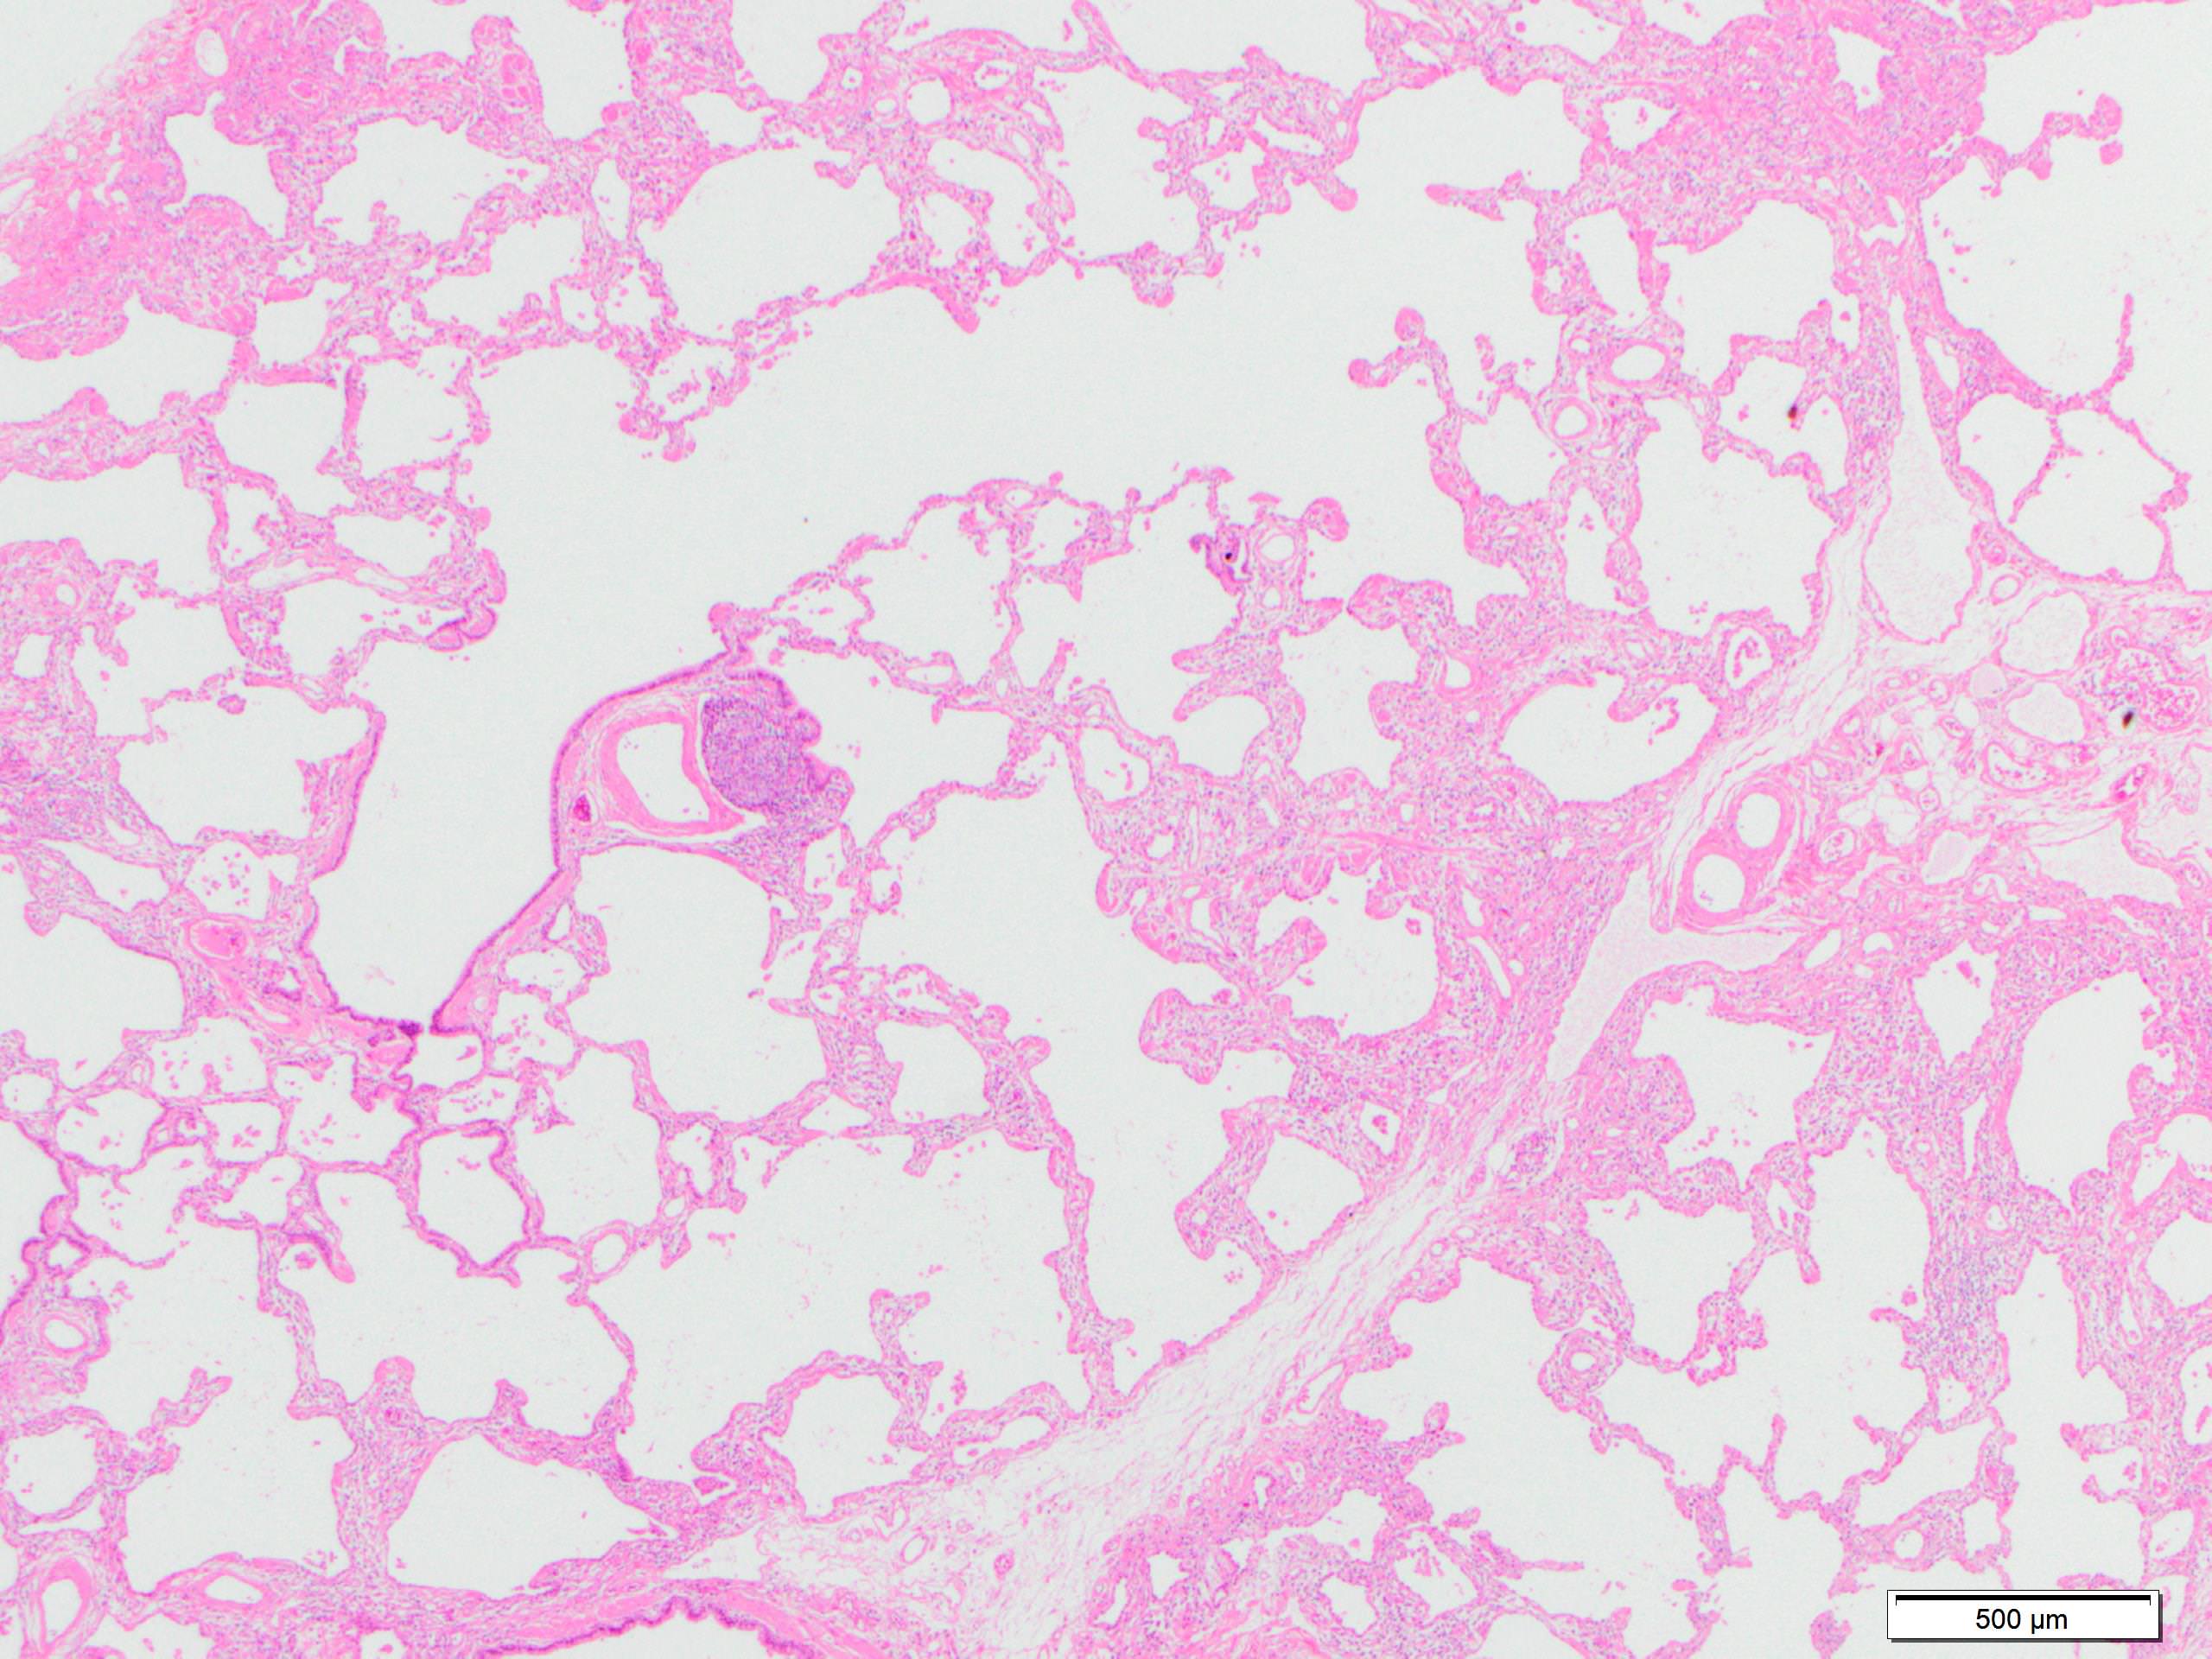

Microscopic (histologic) description

- Since there are few specific findings for NSIP pattern, it is essential to exclude other lung diseases on histology (Am J Respir Crit Care Med 2008;177:1338)

- Characteristic findings of NSIP pattern

- Diffuse and uniform inflammation ("temporal homogeneity") on low power of alveolar wall, bronchovascular bundles and pleura

- There are usually no normal alveolar walls in the affected lobules

- Cellular or fibrotic change

- Lymphocytic or plasmacytic infiltration

- Loose fibrosis

- Lung architecture is frequently preserved

- "Cellular NSIP" or "fibrotic NSIP" can be stated specifically in pathologist report

- Diffuse and uniform inflammation ("temporal homogeneity") on low power of alveolar wall, bronchovascular bundles and pleura

Microscopic (histologic) images

Contributed by Akira Yoshikawa, M.D.